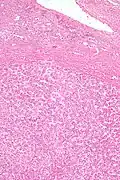

| Micrograph of a hepatic adenoma (bottom of image). H&E stain | |

Pathologic diagnosis

Hepatic adenomas are, typically, well-circumscribed nodules that consist of sheets of hepatocytes with a bubbly vacuolated cytoplasm. The hepatocytes are on a regular reticulin scaffold and less or equal to three cell thick.

The histologic diagnosis of hepatic adenomas can be aided by reticulin staining. In hepatic adenomas, the reticulin scaffold is preserved and hepatocytes do not form layers of four or more hepatocytes, as is seen in hepatocellular carcinoma.

Cells resemble normal hepatocytes and are traversed by blood vessels but lack portal tracts or central veins.